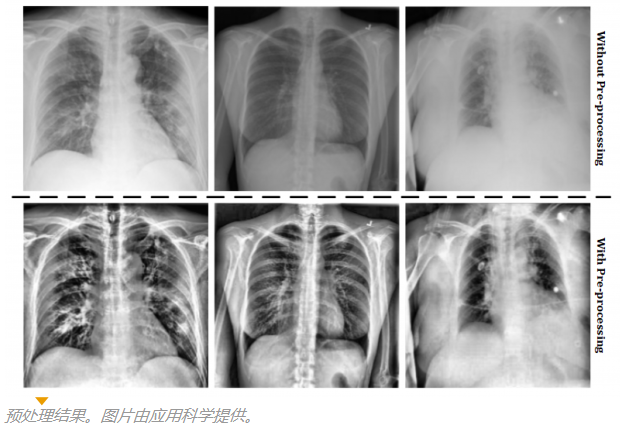

同樣,這項工作分析了基于VGG-16神經網絡的深度學習模型通過軀干X射線識別肺炎和COVID-19的有效性。結果,發表在雜志應用科學, 表明這種方法是在COVID-19的鑒定約100%有效,證明它可以作為一種輔助診斷本病。